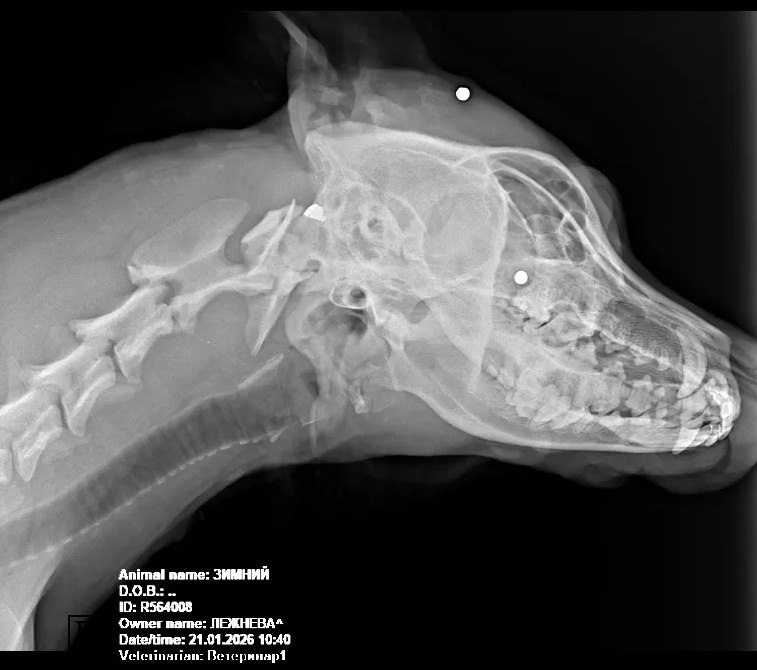

Рентгеновский снимок раненого пса. Фото: t.me/bloknotkrasnodar

Собаку обнаружили на трассе в крайне тяжелом состоянии. Рентген подтвердил наличие пуль в ее теле. У животного диагностированы серьезные травмы головы, воспаление глаз, высокое артериальное давление и заражение крови бактериями. Предположительно, в собаку стреляли из пневматики.